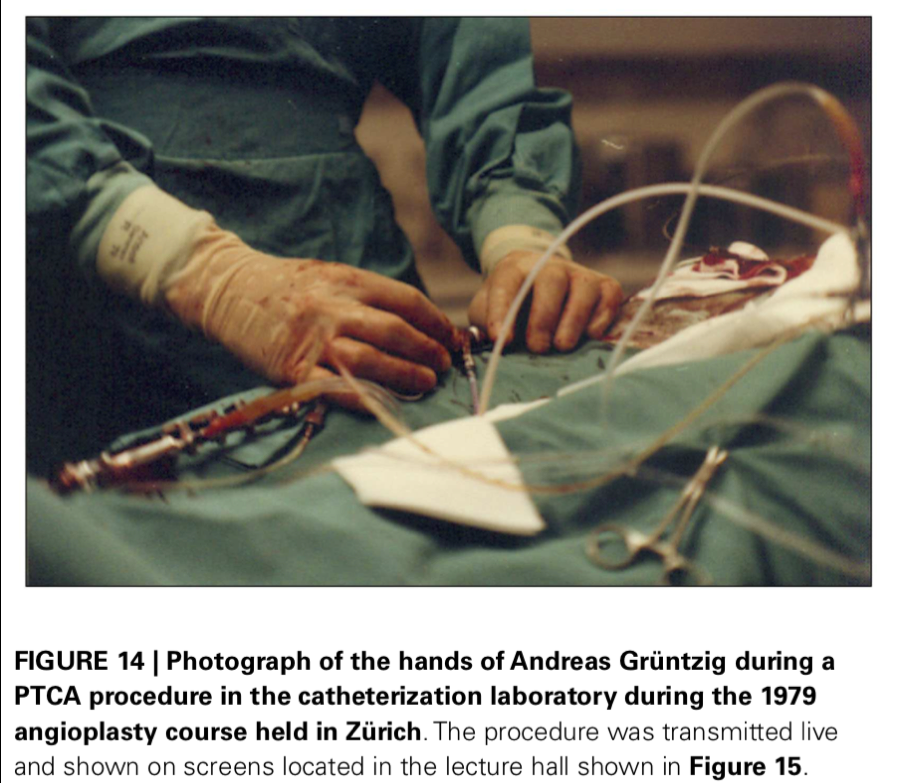

Andreas Grüntzig - 1977: First Coronary Angioplasty - bio - AHA Circulation - 2007

Andreas Gruentzig: The Teaching Genius - article by J. Willis Hurst

Centre of Excellence: Division of Cardiology, Leuven, Belgium - Circulation - 2008